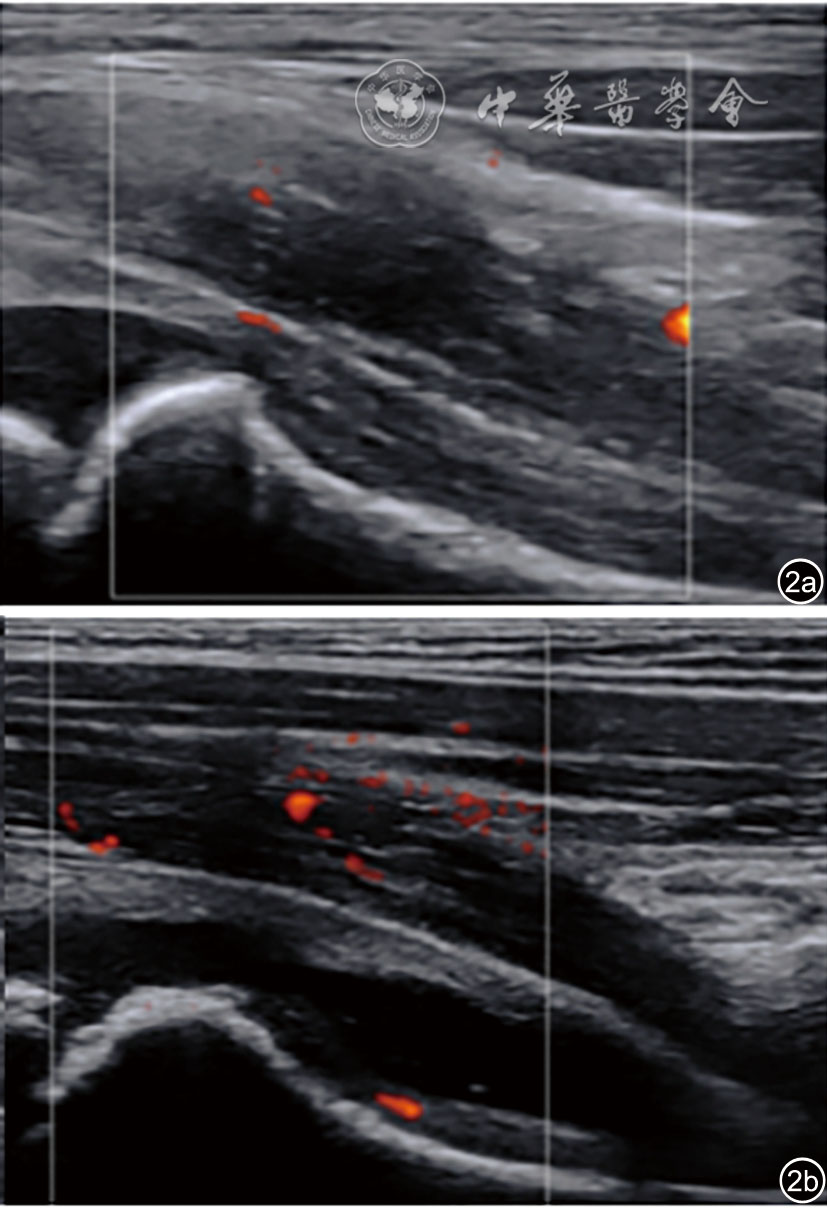

5.关节囊血流信号计数:200例患儿中有30例进行了彩色多普勒超声,均为单侧髋关节受累。30例患儿的健侧与患侧关节囊血流信号计数差异无统计学意义(1.8±0.7 vs 1.7±0.7,P>0.05,图2)。

图2 髋关节暂时性滑膜炎患儿的健侧与患侧关节囊血流信号超声图像。图a示健侧关节囊血流计数为1条;图b为患侧关节囊血流计数为1条